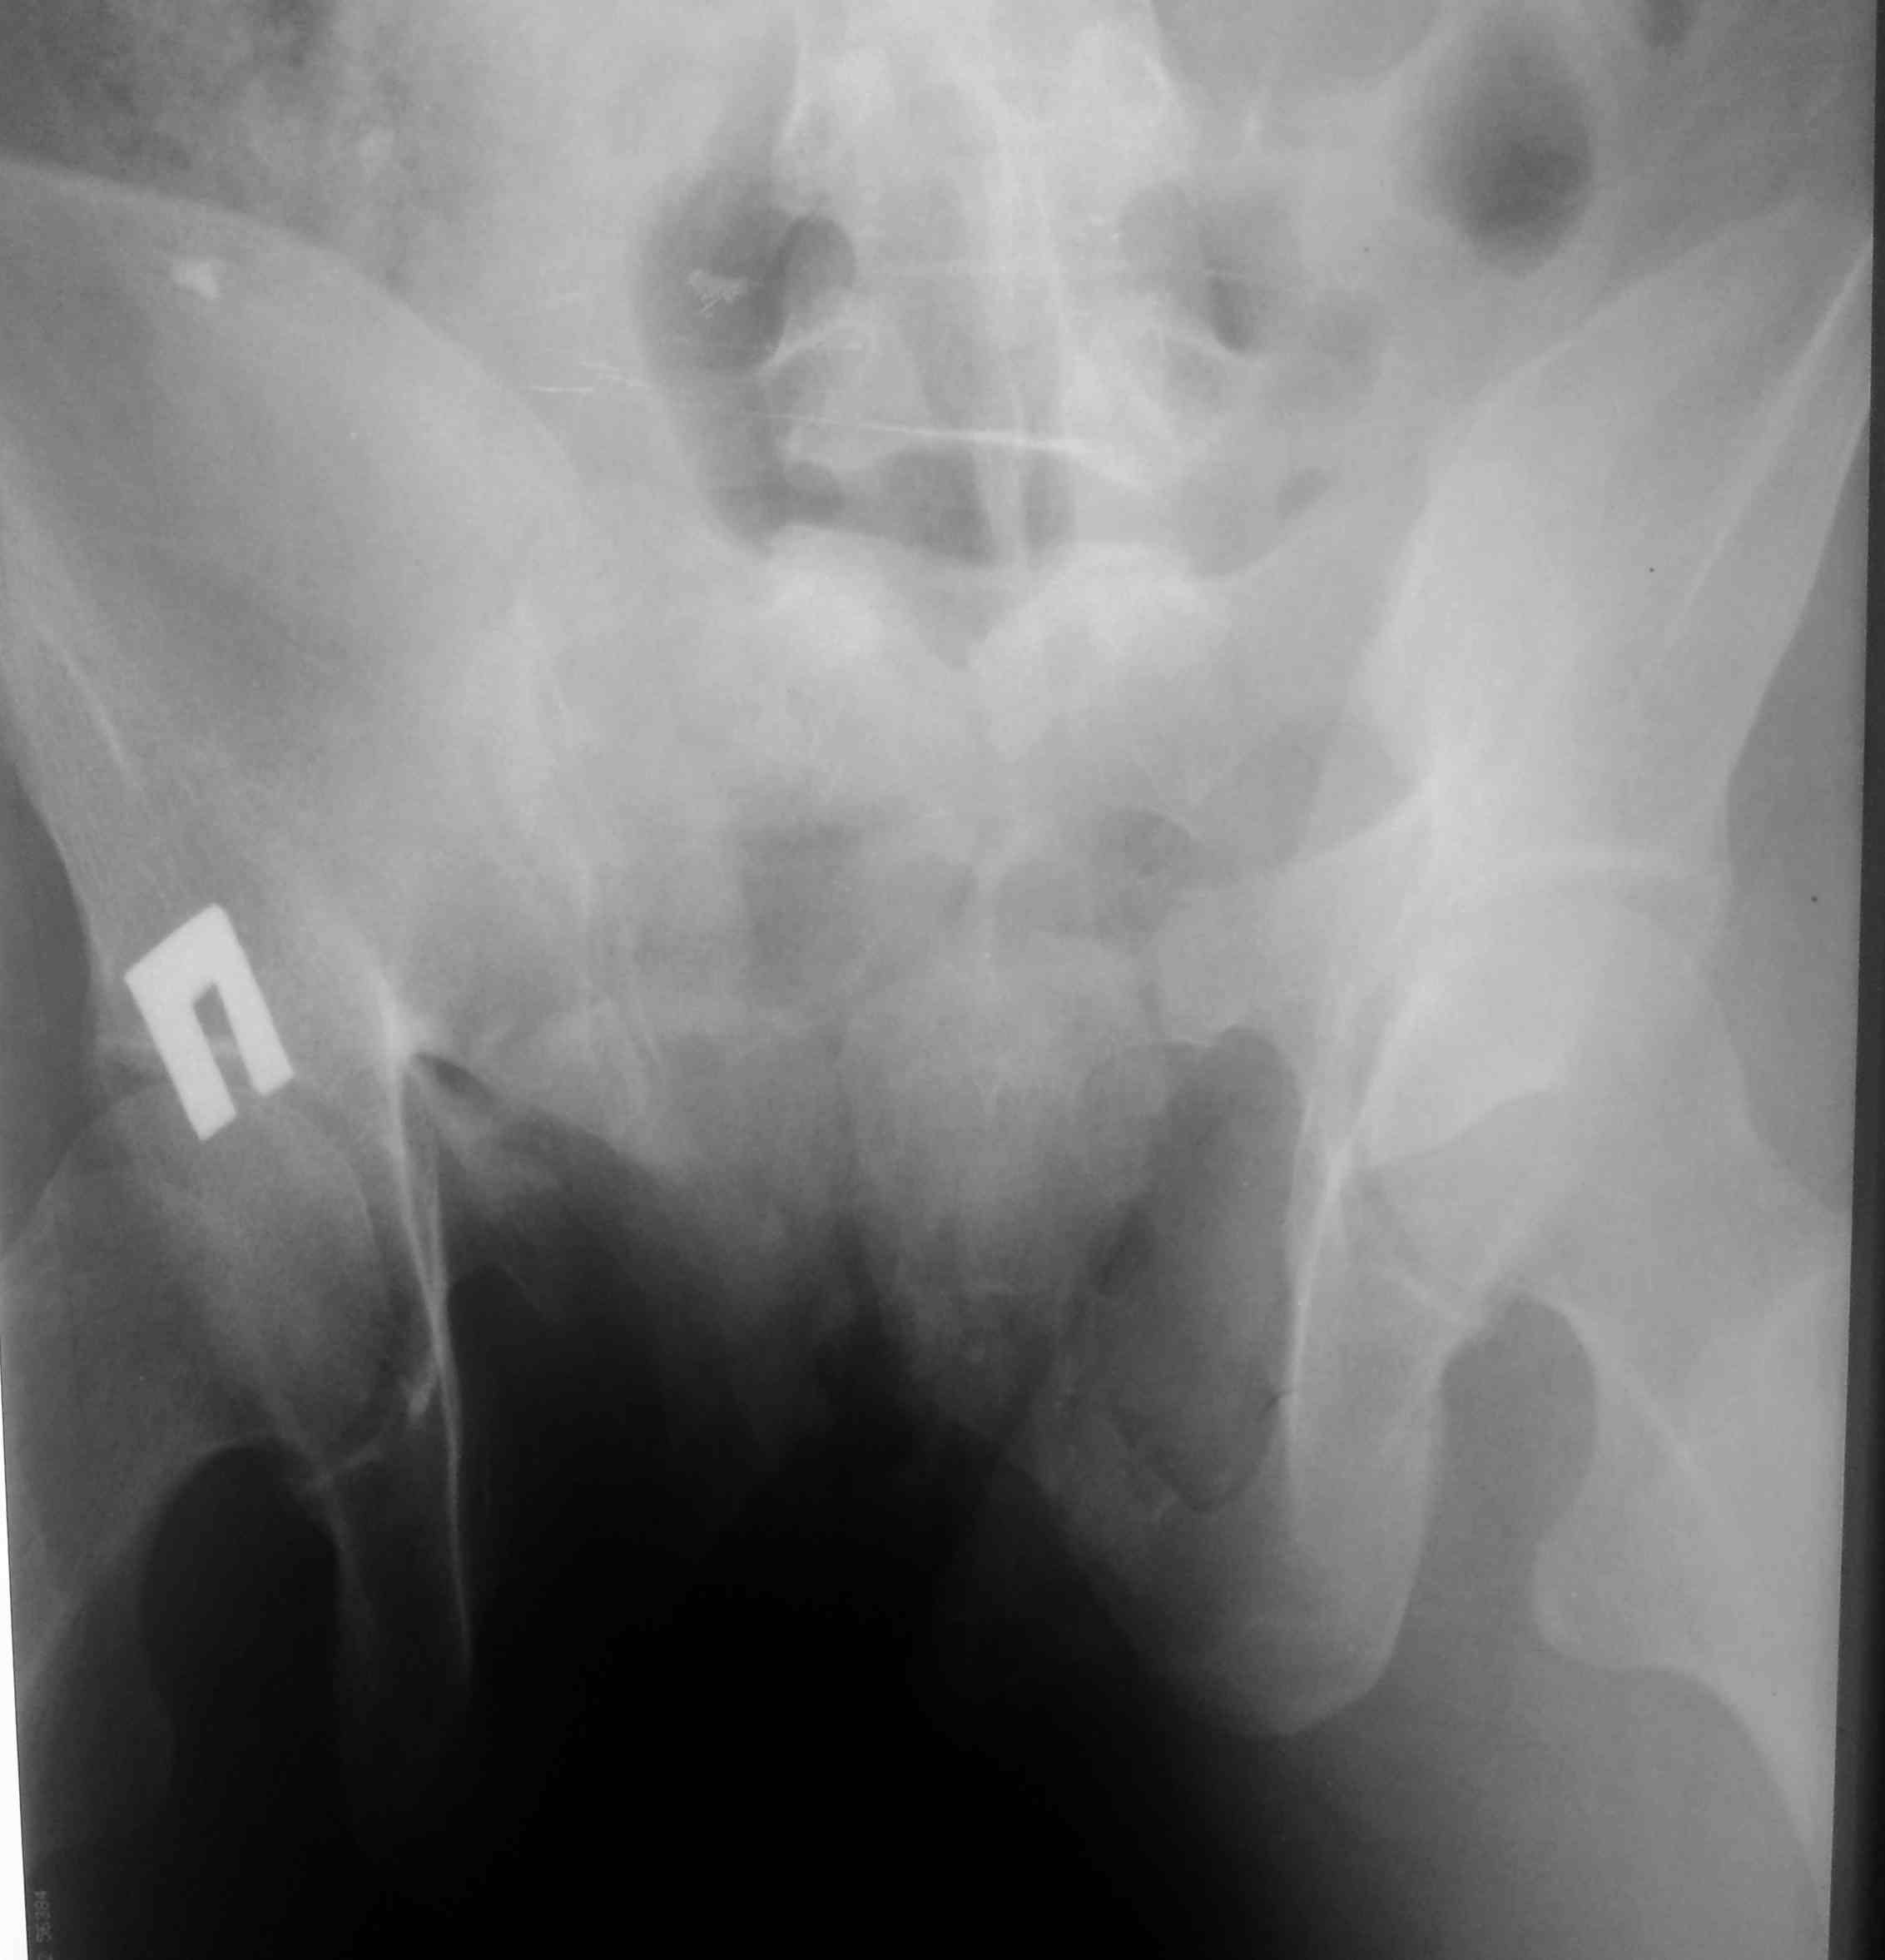

Поступил тяжелый таз Коллеги переслали снимки с дежурства, из снимков , пока только скриннинговый фас. Еще диафизарный перелом плеча. Пациентка около 40 лет, падение с высоты, скорее всего асоциальна. В реанимации, но поступала в сознании. Урологичеких повреждений нет. На мой взгляд, двустороннее повреждение, скорее всего упала на правый бок, сложно- классифицируемое повреждение, справа значительноая компрессия крестца через отверстия, слева перелом через подвздошную кость с вертикальным сдвигом и наружной ротацией. Пока - информация к размышлению, доп проекции доложу.

Здравствуйте! Похоже да, справа- трансфораминальный перелом, а слева перелом через крыло подвздошной кости, но ротация похоже внутренняя. А у нас при поступлении сразу делают только inlet вместо прямой (поскольку последняя часто с проекционными искажениями)

высылаю контрольные снимки на вытяжении, правую половину таза подрепонировали вручную, за лево - скелетка. Дополнительно, левое плечо - диафиз, множественные переломы ребер слева. Стала хуже по легким. Пока план - при улучшении по легким - передняя рама + илиосакральные винты справа, при улучшении - расслабляем переднюю раму, открыто синтезируем подвздошную кость задним доступом, обратно затягиваем аппарат. Плечо - когда получится